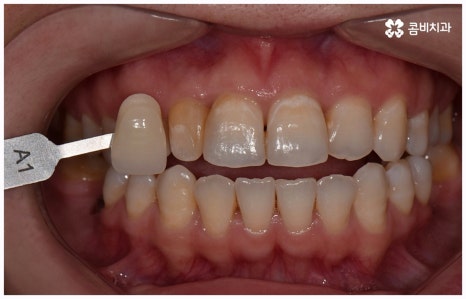

이러한 치아 상실에 대해 예전에는 틀니와 브릿지 시술을 많이 받았지만 요즘 대세는 임플란트 식립이라고 할 수 있어요. 틀니처럼 탈락의 위험이 잦거나 음식을 먹을 때 제약이 크게 따르지 않으며 브릿지처럼 양 옆 치아를 제거하지 않아도 되는 임플란트는 치아가 빠진 잇몸에 직접 티타늄 인공 치근(픽스처)을 심은 다음 지대주(연결 부위)를 이어주고 크라운(치아 머리 보철물)을 씌워 수복을 하는 것이기 때문에 저작 능력의 회복이 탁월하고 겉에서 봤을 때 거의 자신의 치아와 다름없이 자연스럽게 보인다는 장점으로 인해 많은 분들이 선호하시는 거예요.

임플란트는 관리를 철저하게 해 준다면 거의 반영구적으로 쓸 수 있다고 알려져 있을 만큼 잘 유지 관리하는 것이 굉장히 중요한데, 그 첫 단계가 정확한 위치와 각도로 식립하는 과정이라고 할 수 있어요. 임플란트가 잘못된 위치에 식립되거나 너무 깊게 또는 얕게 식립되면 교합이 잘 맞지 않고 저작 활동을 할 때 무리가 가 잇몸병을 유발함으로써 임플란트의 수명을 줄일 수 있기 때문인데, 이때 임플란트 제작시 커스텀 지대주를 사용하면 환자분들의 구강 구조에 정확하게 맞는 각도로 보철물을 식립할 수 있어서 더욱 편안한 사용을 할 수 있을 거예요. 식립 후 너무 많이 딱딱하거나 끈끈한 음식은 조심하시는 편이 좋으며, 이후 꾸준하고 지속적인 검진 및 스케일링 치료를 통해 위생을 청결하게 해 주면 임플란트 수명을 연장하는데 도움이 될 수 있습니다.